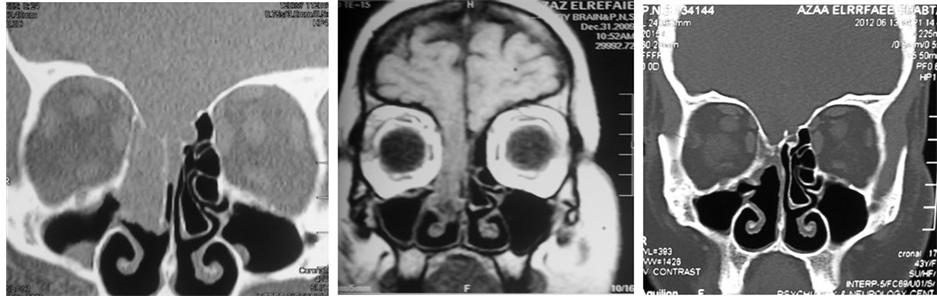

The site of the leak was localized preoperatively in the radiological examination in all cases (Table 1). No cases had multiple sites of leak in our series. A meningoencephalocele was found in 13 cases (48%) (Figure 2).

Figure 2. (a) Coronal CT scan PNS; (b) Coronal T1 weighted MRI showing a right sided huge meningoencephalocele, involving right fovea ethmoidalis and cribrifom plate; (c) Follow up CT scan 12 months after the repair showing success of the repair.